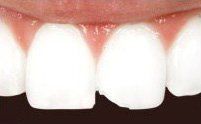

Smile Restoration Procedure

Patient needed multiple restorations, decay removed from upper teeth, crowns placed from canine to canine. Patient Missing 1st lower molar, implant and crown placed, chewing function restored. 2nd molar cracked, causing severe pain, nerve removed from tooth with root canal therapy